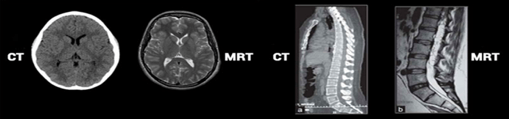

Ovdje je prikazan kranijum u transverzalnoj ravni u T1 i T2 vremenu. Uočljiva je razlika koja ukazuje na to da je u T1 vremenu bijela masa svjetlija, u odnosu na sivu masu i cerebrospinalnu tečnost, dok su u T2 vremenu ove strukture predstavljene kao negativ T1 vremena.